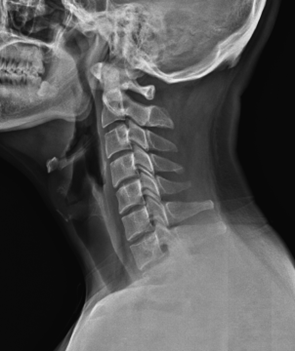

X-ray를 찍어보니 역시나

일자목(거북목 증후군)이 확연했고

C2-C3 (목뼈 2-3번) 사이의 간격

좁아져 있는 것도 확인됐습니다.

그림4.png 촬영 일시: 2025.06.19

<Fig 1. 이상 소견 없는 뇌 MRI>